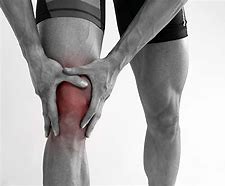

무릎 통증 원인과 치료방법 총정리!

무릎 통증의 원인과 그에 맞는 치료법을 찾고 계신다면 여러가지 무릎 통증의 원인과 그에 맞는 치료법이 정리되어 있으니 자신에게 맞는 원인과 치료법을 확인해 보시기 바랍니다. 무릎 통증